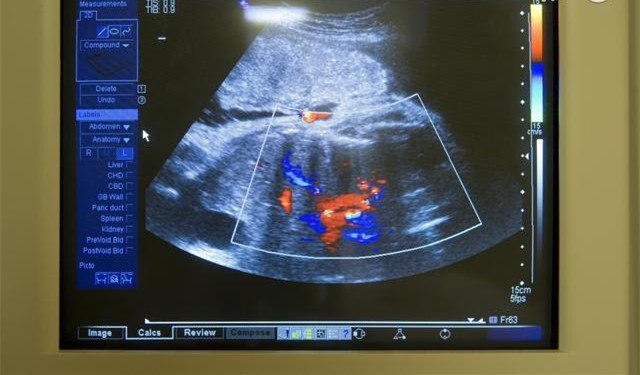

此时已经完全可以区分出手臂和腿,而且胎儿的长度也有很大变化,手指和脚趾也成形了。此时胎儿的皮肤薄而透明,能清晰地看到胎儿的血管,胎儿的脸部形成了眼皮,开始显露出胎儿的鼻子和嘴唇,同时开始形成睾X丸或卵X巢生X殖器组织。